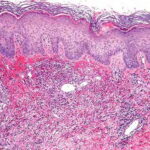

Histopathology. Typically, a dense perivascular infiltrate composed largely of neutrophils is seen assuming a bandlike distribution throughout the papillary dermis . Some of the neutrophils may show nuclear fragmentation (leukocytoclasis). In addition, the infiltrate may contain scattered lymphocytes and histiocytes and occasional eosinophils. The density of the infiltrate varies and may be limited in a small proportion of cases. Vasodilation and swelling of endothelium with moderate erythrocyte extravasation and prominent edema of the upper dermis are characteristic. In some instances, subepidermal blister formation may result. Extensive vascular damage is not a feature of Sweet’s syndrome. The histologic appearance varies depending on the stage of the process. In later stages, lymphocytes and histiocytes may predominate. Sweet’s-like neutrophilic dermatoses often show a similar histologic picture. However, the reaction pattern may on occasion be quite different, for instance, manifesting as deep subcutaneous localized suppurative panniculitis. The infiltrate of Sweet’s syndrome is not characteristic enough to exclude infection on histologic findings alone. As always, to arrive at the correct interpretation of a neutrophilic infiltrate, cultures need to be obtained and special stains need to be performed to exclude an infectious etiology. |